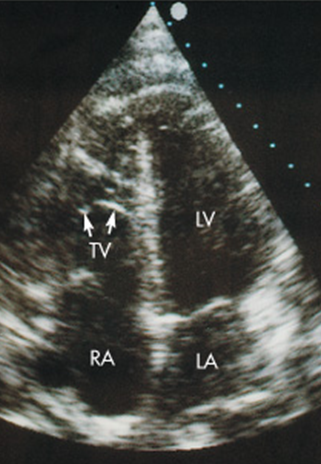

Tricuspid Atresia

Ebstein’s Anomaly of Tricuspid Valve